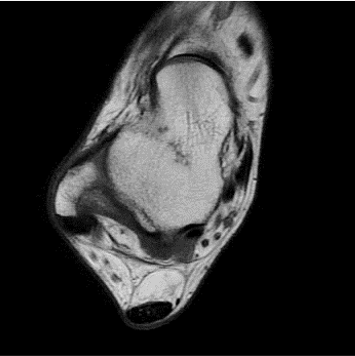

standard

384 x 256 (4 NEX)

3:02 minIAI (Innovative AI)

384 x 256 (2 NEX)

1:30 minReduced Scan Time

384 x 256 (2 NEX)

1:30 minstandard

384 x 256 (4 NEX)

2:59 minIAI (Innovative AI)

384 x 256 (2 NEX)

1:28 minReduced Scan Time

384 x 256 (2 NEX)

1:28 minConventional